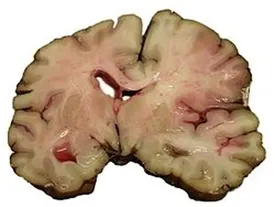

عضو هیئت مدیره انجمن سکته مغزی ایران با اشاره به این مهم که سکته مغزی دومین علت مرگ و میر در ایران محسوب میشود، بیان داشت: متاسفانه میزان بروز سکته مغزی در ایران ۱۰سال جوانتر و ۱/۵ برابر متوسط جهانی است.

یک متخصص مغز و اعصاب گفت: اولین و مهم ترین عامل بروز سکتههای مغزی، سن است. یعنی هر چه سن بالاتر رود، شانس بروز سکته های مغزی هم به مراتب بیشتر میشود.

سکته مغزی چهارمین عامل مرگ و میر در دنیا شناخته میشود و حتی اگر منجر به مرگ افراد نشود، لطمات جبران ناپذیر جسمانی به همراه دارد؛ اما سکته مغزی چه علایمی دارد و چطور می توان آسیب های ناشی از آن را در زمان وقوع سکته کاهش داد؟